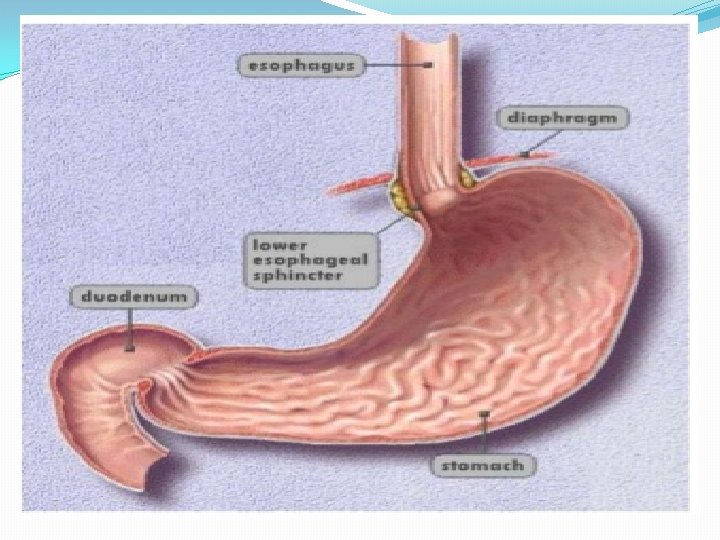

The Esophagus Gastroesophageal Reflux Disease (GERD) Gastroesophageal reflux (GER) : retrograde movement of gastric contents across the lower esophageal sphincter (LES) into the esophagus.

Pathophysiology Antireflux barrier: *lower esophageal sphincter (LES) *the crura of the diaphragm *gastroesophageal junction anatomy